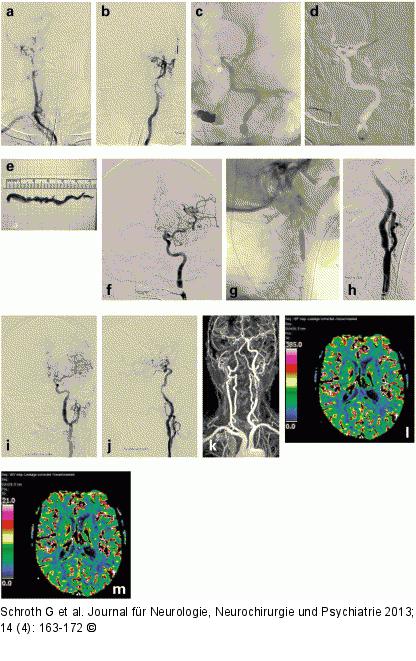

Abbildung 7a-m: Schlaganfall-Management 73-jähriger Mann ohne Vorerkrankungen mit plötzlicher Hemiparese rechts und Aphasie; NIHSS 11. (a) Im Kontrast-MRA Verschluss beider Karotiden, nur kleine linkshemisphärische DWI-Läsionen mit großem DWI/PWI-Mismatch. Die Injektion in den Truncus brachiocephalicus bestätigt den ICA-Verschluss rechts. Beide Hirnhälften werden über die Rami communicantes posteriores aus dem vertebrobasilären Stromgebiet mit Blut versorgt. (b) Frischer Verschluss der ICA links im Übersichtsangiogramm. (c) Nach Passage des Verschlusses der A. carotis interna Einlage eines Stent-Retrievers in die A. cerebri media unter „flow arrest“. (d) Platzierung eines 5-F-Aspirationskatheters über den Draht des Stent-Retrievers vor den Thrombus. (e) Dokumentation des mittels „Triple-Access“ retrahierten Thrombus. Nach (f) Rekanalisation der intrakraniellen Gefäße durch simultane Rücknahme des Stent-Retrievers und Aspirationskatheters, der während dieser Aktion ebenso wie der Ballonkatheter an der Schädelbasis maximal aspiriert wird, erfolgt als letzter Schritt die Stenteinlage in die zuvor verschlossene ICA, wobei der Hirnkreislauf vor einer eventuellen erneuten Embolie mit einem distalen Filter geschützt ist (g, h). (i, j) DSA-Abschlusskontrolle: Beide Arteriae cerebri anteriores füllen sich über die wiedereröffnete linke A. carotis interna. Die MR-Kontrolle 3 Monate später zeigt im Kontrast-MRA die offene linke Karotis mit Signalauslöschung im Stentbereich (k) und beide Hirnhälften normal perfundiert. (l, m) Leakage-korrigierte CBF- und CBV-Parameterbilder. |

Abbildung 7a-m: Schlaganfall-Management